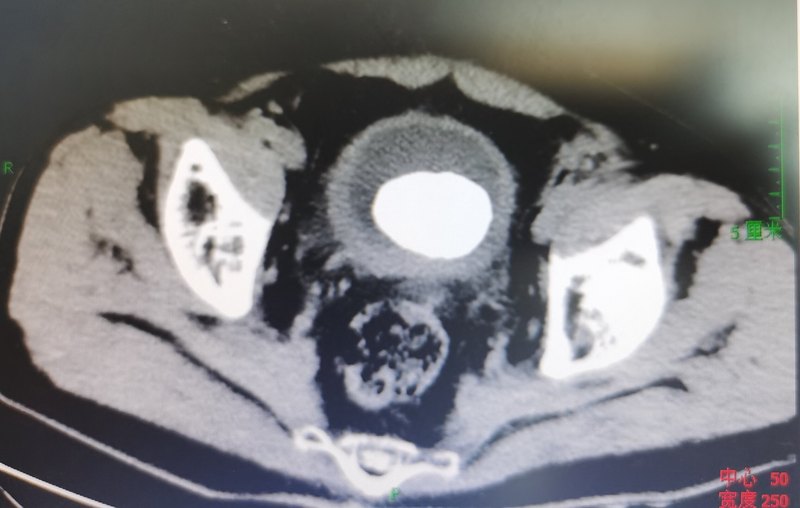

膀胱大结石一朝解除

患者男性,79岁,近期出现血尿,同时伴有尿频,尿急,偶有尿痛。患者来院就诊。经完善泌尿系ct检查:如下膀胱内大结石,直径约5cm。若按照以前方案,手术需采取下腹纵形切口,开放切开取石。这种方法,随可以一次性取出结石,但术后可能会出现伤口漏尿,感染可能,同时下腹会留下很长的手术瘢痕。我们采取微创的经尿道肾镜下EMS碎石,边碎石边吸出碎石渣,提高手术效率,一次性解决95%以上的结石。对患者创伤达到最小,同时患者恢复很快。术后复查CT如下:目前泌尿系结石治疗已经进入微创治疗时代,逐渐摈弃开放手术。为患者带来最大的受益。